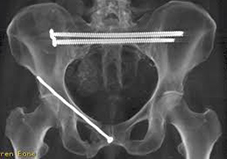

Compared with triangular osteosynthesis fixation, a new two-transsacral-screw fixation technique for vertically unstable cadaveric pelvic fractures was shown to be a viable alternative that provides biplanar stability, according to study findings.